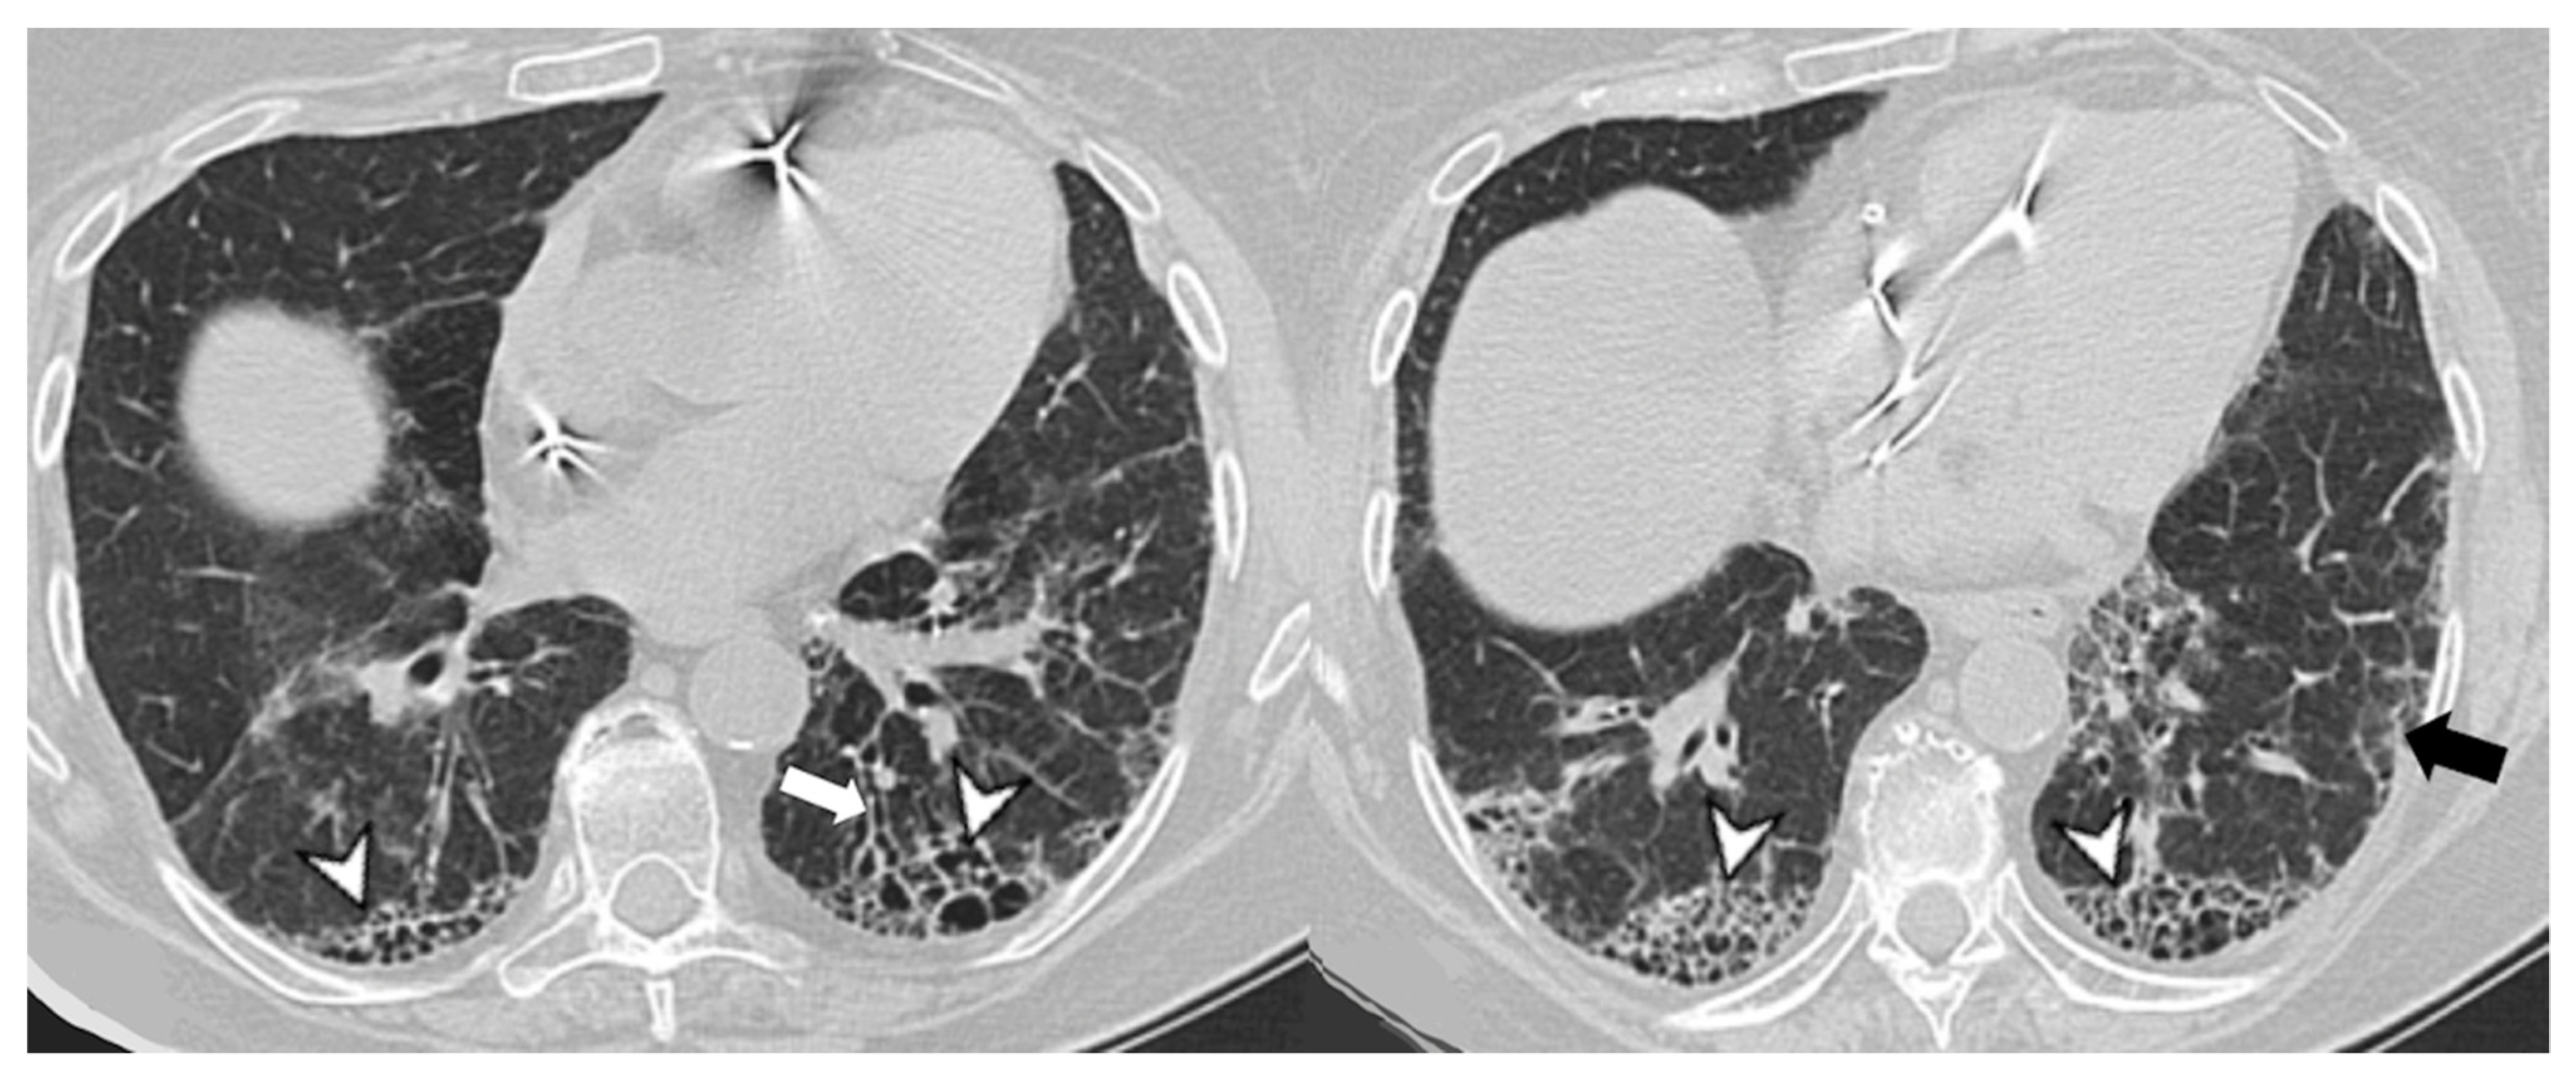

| Lesions | GGO, reticulations, consolidations | consolidations, GGOs | |

| Distribution | Homogeneous; lower lung lobes, along bronchovascular bundles and lung periphery; loss of volume of lower lobes | Patchy; peripheral lower lobes or along the bronchovascular bundles | |

| CT pattern | NSIP OP NSIP-OP UIP DAD-unclassifiable | 50% 20% 25% 10% +/− | 20% 50% 25% <5% ++ |